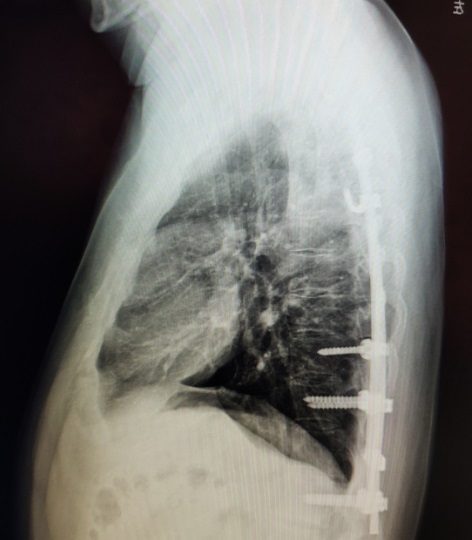

入院查体,患者左侧胸壁突起,右侧低平,呈不对称型鸡胸。背部有长约30cm长的手术疤痕。X线检查提示前胸壁双影。经充分术前准备,我们采用无管技术为患者实施了微创手术。术中使用两条钢板做塑形,手术历经30分钟完成,操作顺利,未出现并发症,术后畸形完全消失。